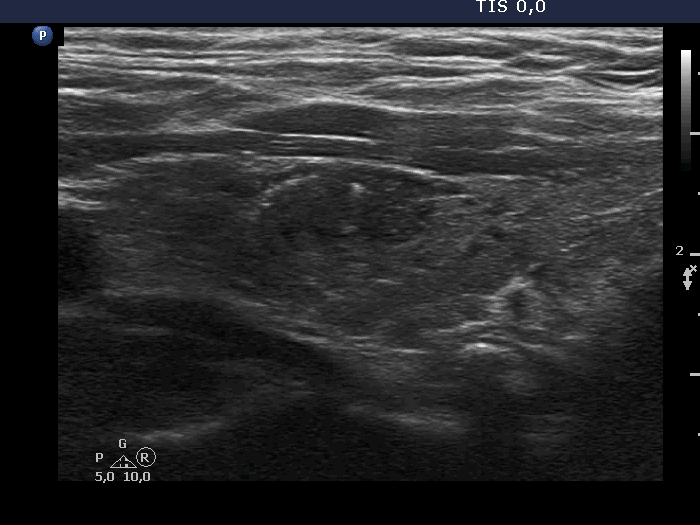

100 consecutive cases of papillary cancer - case 084 (ultrasonographic picture 7)

Left lobe, another longitudinal scan. The nodule has a few bright echogenic granules.